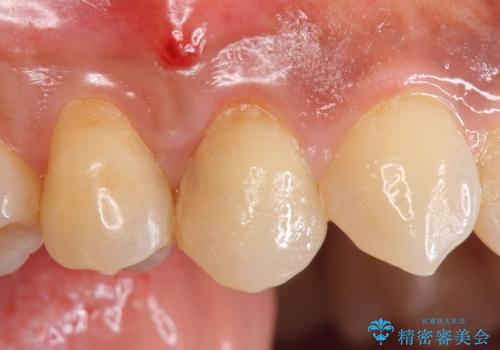

- 左下奥歯の銀歯を白くしたいと来院された方の症例です。

銀歯を除去後、セラミックインレーによる修復を行いました。

当院のセラミックインレーはemaxという強度と審美性に優れた材料を使用しています。

またプレス方式でインレーを製作しているため、削り出しで製作するCADCAMより優れた適合性も持ち合わせており、虫歯が再発しにくい修復物です。